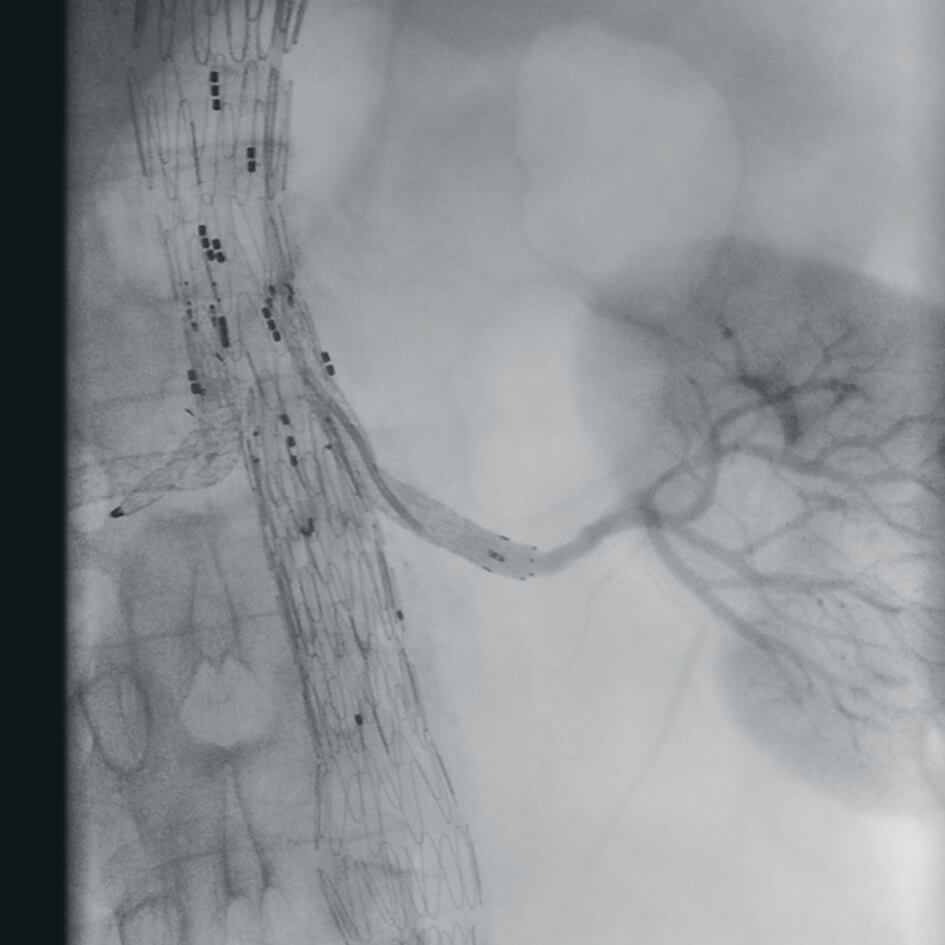

Полное отсутствие искажений снимков в сочетании с высоким динамическим диапазоном широко востребованы как при сложных операциях в нейрохирургии, сосудистой хирургии, инвазивной радиологии, так и в гибридных областях применения, а также в ортопедии, травматологии. В сосудистой хирургии особенно важны высокий динамический диапазон и пространственное разрешение, обеспечивающие детальную визуализацию даже мельчайших сосудов. Специализированное программное обеспечение SmartVascular позволяет проводить настройку системы для васкулярных операций и сосудистой хирургии.

Впервые в мировой практике в Vision RFD 3D используется невероятно компактный моноблочный генератор для импульсной рентгеноскопии с увеличенной резервной мощностью и вращающимся анодом рентгеновской трубки для улучшения качества изображений при минимальной интенсивности облучения. Продолжительность импульсов можно регулировать в диапазоне от 7 до 40 мс, что существенно повышает четкость снимков. Vision RFD 3D отлично подходит для использования в клинических процедурах типа: чрескожная транслюминальная коронарная ангиопластика или коронарная ангиография.

- программный пакет для сосудистой хирургии,

- субтракционная ангиография с применением СО2.